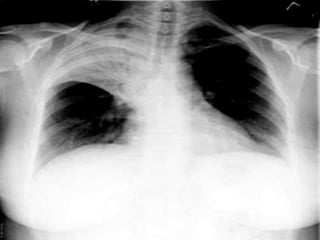

HILUM OVERLAY SIGN

• The hilum overlay sign refers to an appearance on frontal

chest radiographs of patients with a mass projected at the

level of the hilum which is in fact either anterior or posterior

to the hilum.

• When a mass arises from the hilum, the pulmonary vessels

are in contact with the mass and as such their silhouette is

obliterated.

• The sign was first described by Benjamin Felson

HILUM OVERLAY SIGN •The hilum overlay sign refers to an appearance on frontal chest radiographs of patients with a mass projected at the level of the hilum which is in fact either anterior or posterior to the hilum. • When a mass arises from the hilum, the pulmonary vessels are in contact with the mass and as such their silhouette is obliterated. • The sign was first described by Benjamin Felson

• #16 SILHOUETTE SIGN OF THE HIKA . USED TO DETERMINE THE LOCALISATION OF A LESION IN THE HILAR REGION IN CHEST XRAYS .